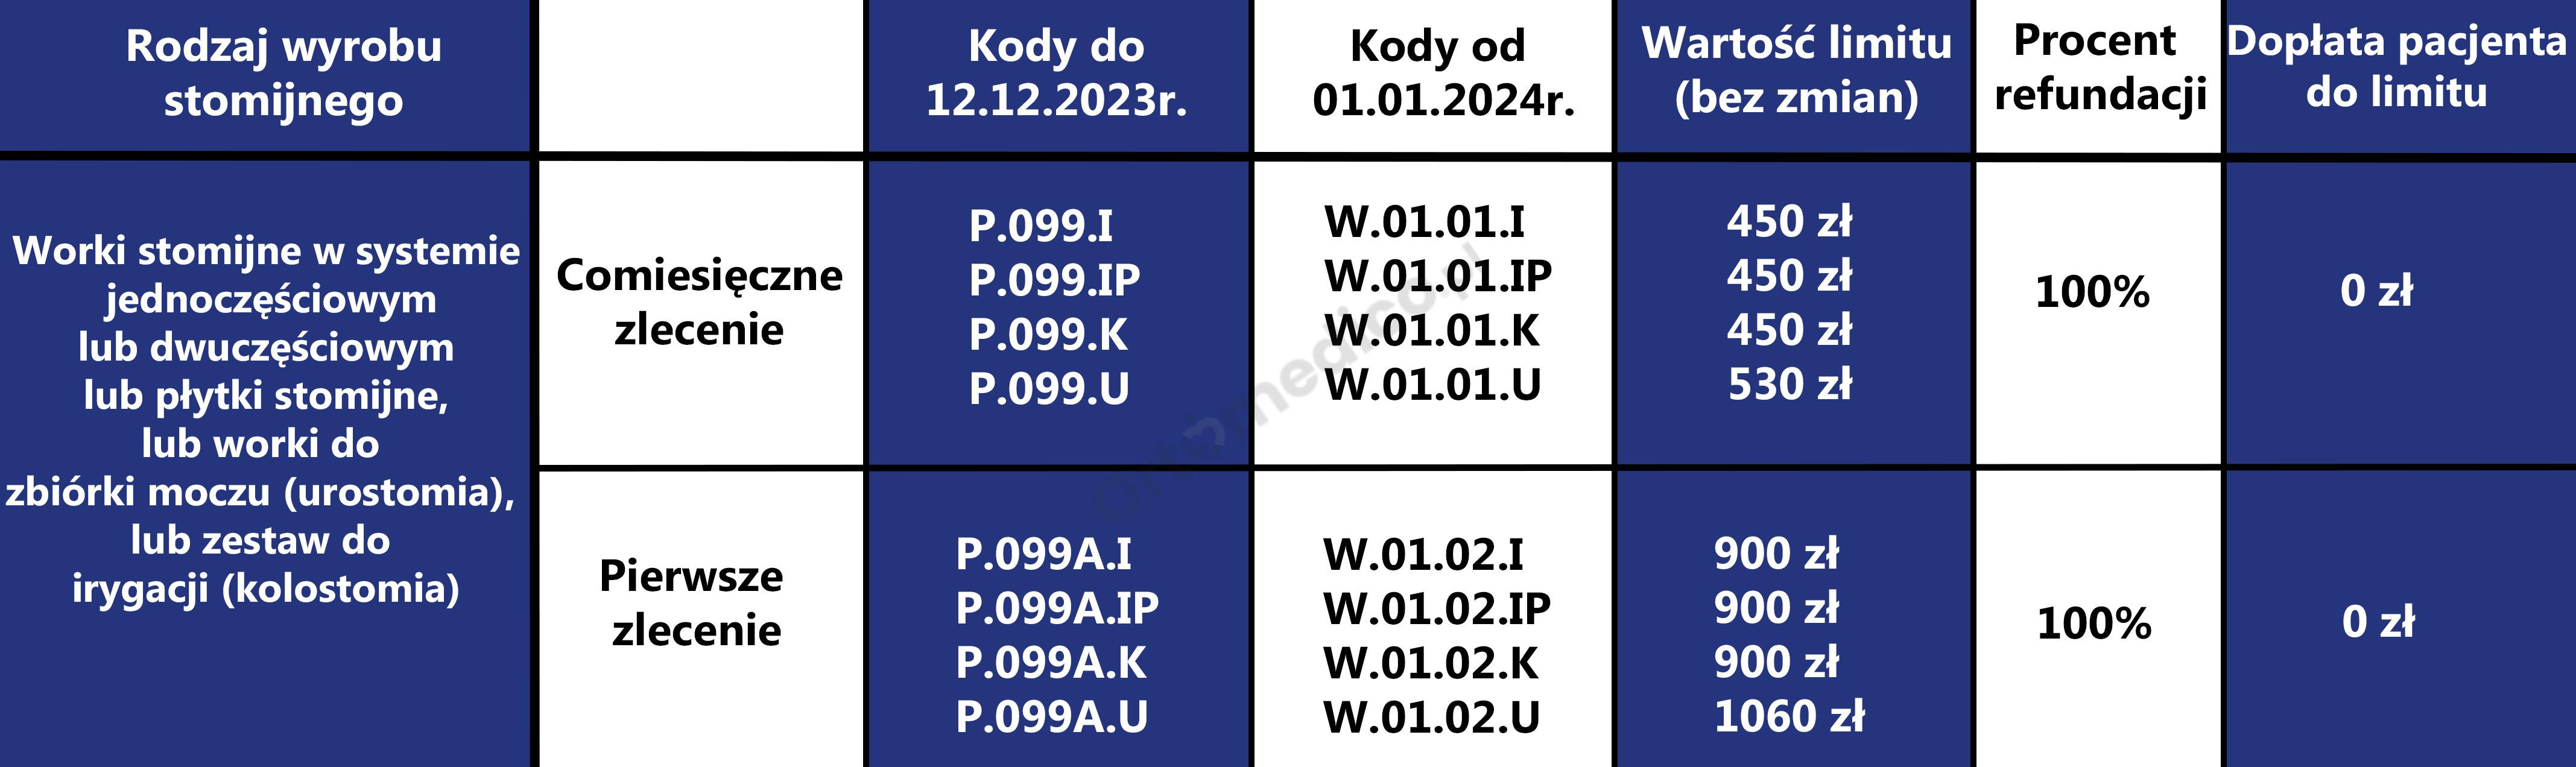

Od 1 stycznia 2023 roku zmianie uległa refundacja wyrobów stomijnych. Ustanowiono 2 zlecenia na sprzęt stomijny (P.99 worki i płytki i P.141 akcesoria) oraz osobne zlecenie (P.99.A, P.141.A) dla pacjentów nowo operowanych z podwójnym limitem. Podwyższono limity: w kolostomii i ileostomii do 450 zł ; w urostomii do 530 zł, akcesoria 120 zł w tym 20% dopłaty pacjenta. Wystawiający zlecenie będzie zlecał ryczałt lub jego część lub jego wielokrotność w przypadku pacjentów z 47ZN, 47ZND, 47DN.

Więcej informacji znajdziesz w artykule

Od 1 stycznia 2024 roku będą obowiązywały nowe zasady refundacji wyrobów stomijnych przez Narodowy Fundusz Zdrowia. Zgodnie z rozporządzeniem Ministra Zdrowia z dnia 13 października 2023 r. zmieniającym rozporządzenie w sprawie wykazu wyrobów medycznych wydawanych na zlecenie kwoty limitu pozostają bez zmian, zmienia się natomiast udział pacjenta w limicie w wyrobach stomijnych dla osób dorosłych i dzieci do 18. roku życia.

Po dokładne informacje zapraszamy do artykułu